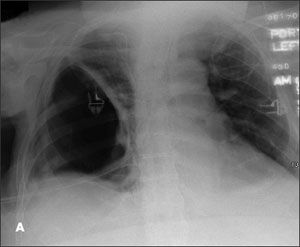

A chest radiograph showed herniation of a large right lung bulla through the intercostal space into the chest wall (A). This was confirmed on a CT scan of the thorax (B) with coronal reconstruction (C). His left lung was normal.

The herniation presents as a chest wall mass that may be asymptomatic or associated with pain or dyspnea. The mass is noncrepitant, which distinguishes it from subcutaneous emphysema and herniated lung parenchyma. Its dimensions change with the respiratory cycle: increasing with inspiration and decreasing with expiration. The hernia is usually easily reducible.

The diagnosis is readily made by imaging. CT provides additional information about the state of the underlying lung and orifice of the hernia.